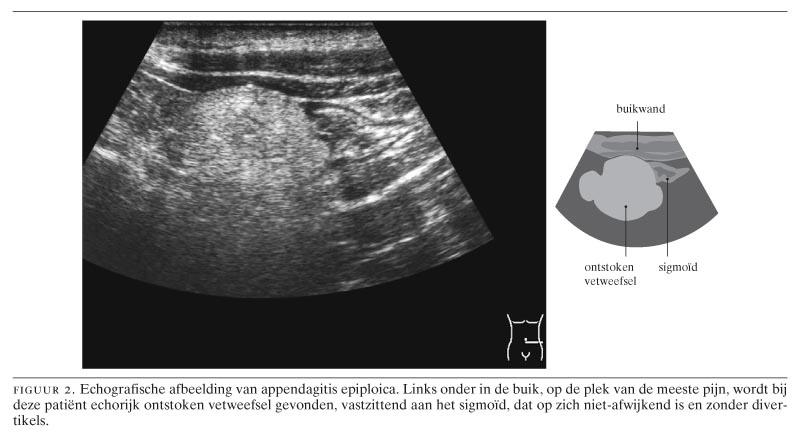

De karakteristieke echografische bevinding bij appendagitis epiploica is een 1 tot 4 cm grote intra-abdominaal gelokaliseerde massa van echorijk ontstoken vetweefsel, dat vastzit aan het colon, exact op de plek van de meeste pijnklachten (figuur 2).5 9 Met CT bevestigt men de diagnose door het aantonen van een karakteristieke dense ring in of rondom het ontstoken vetweefsel (figuur 3), hetgeen overeenkomt met oedemateus verdikt visceraal peritoneum rondom de ontstoken appendix epiploica.5 6 9